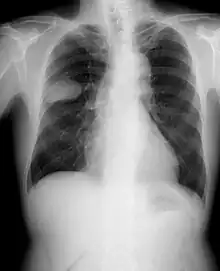

Radiographie de la poitrine montrant une tumeur cancéreuse dans le poumon gauche sous forme d'une opacité ovale.

La radiographie thoracique est la première mesure à prendre si un patient se plaint de symptômes pouvant suggérer un cancer du poumon. Ceci peut révéler une masse évidente, un élargissement du médiastin (qui suggère une extension aux ganglions lymphatiques qui s'y trouvent), une atélectasie (affaissement), une inflammation (pneumonie) ou un épanchement pleural. En l'absence de signes radiographiques, mais si les soupçons sont élevés (par exemple, un gros fumeur avec hémoptysie), une bronchoscopie ou un scanner peuvent donner l'information nécessaire. La bronchoscopie ou la biopsie guidée par scanner sont souvent utilisées pour identifier le type de tumeur[3].